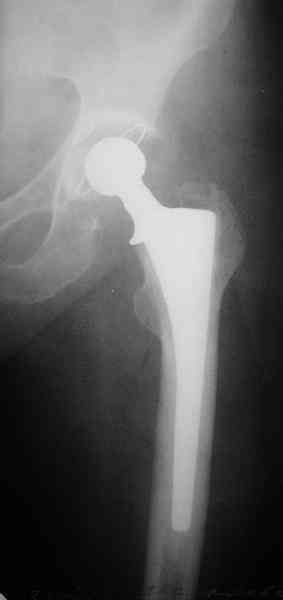

Перелом бедра, через неделю после эндопротезирования.

Уважаемые участники форума, просьба высказать Ваши мнения по представленному случаю. На прошлой неделе пациентке 74 лет, было выполнено цементное эндопротезирование тазобедренного сустава по поводу перелома шейки бедра.

Активизирована на следующий день, ходила с костылями, нагрузка полная. Дело близилось к выписке, когда она, поскользнувшись, упала в палате и получила то, что видите на снимках.Что бы Вы стали делать в подобной ситуации? Заранее спасибо.

A female 74 y.o. fell at day 7th after cemented THA. The femur is split from the tip of the troch (preexisted crack?) and fracture goes below the tip of the stem. Images attached. What type the fracture is according to Vancouver classification? We consider some kind of plating. What type of implant would you prefer? How long the plate should be? Is cable technique necessary? Grafting? Any probable pitfalls to concern? THX!